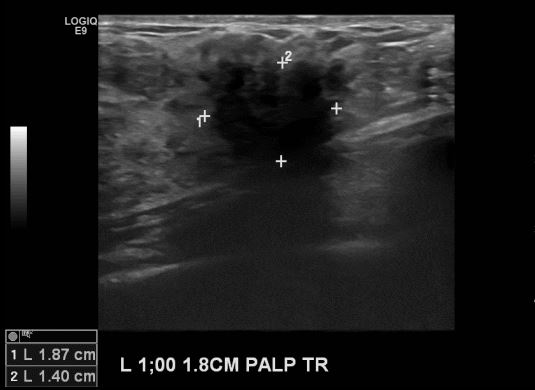

상기환자 유방에 만져지는 멍울로 내원하신 40대 여성분으로 본원 초음파상 좌측 1시

방향에 만져지는 멍울 조직검사 시행하여 좌측 침윤성 유관암 진단 되었습니다.